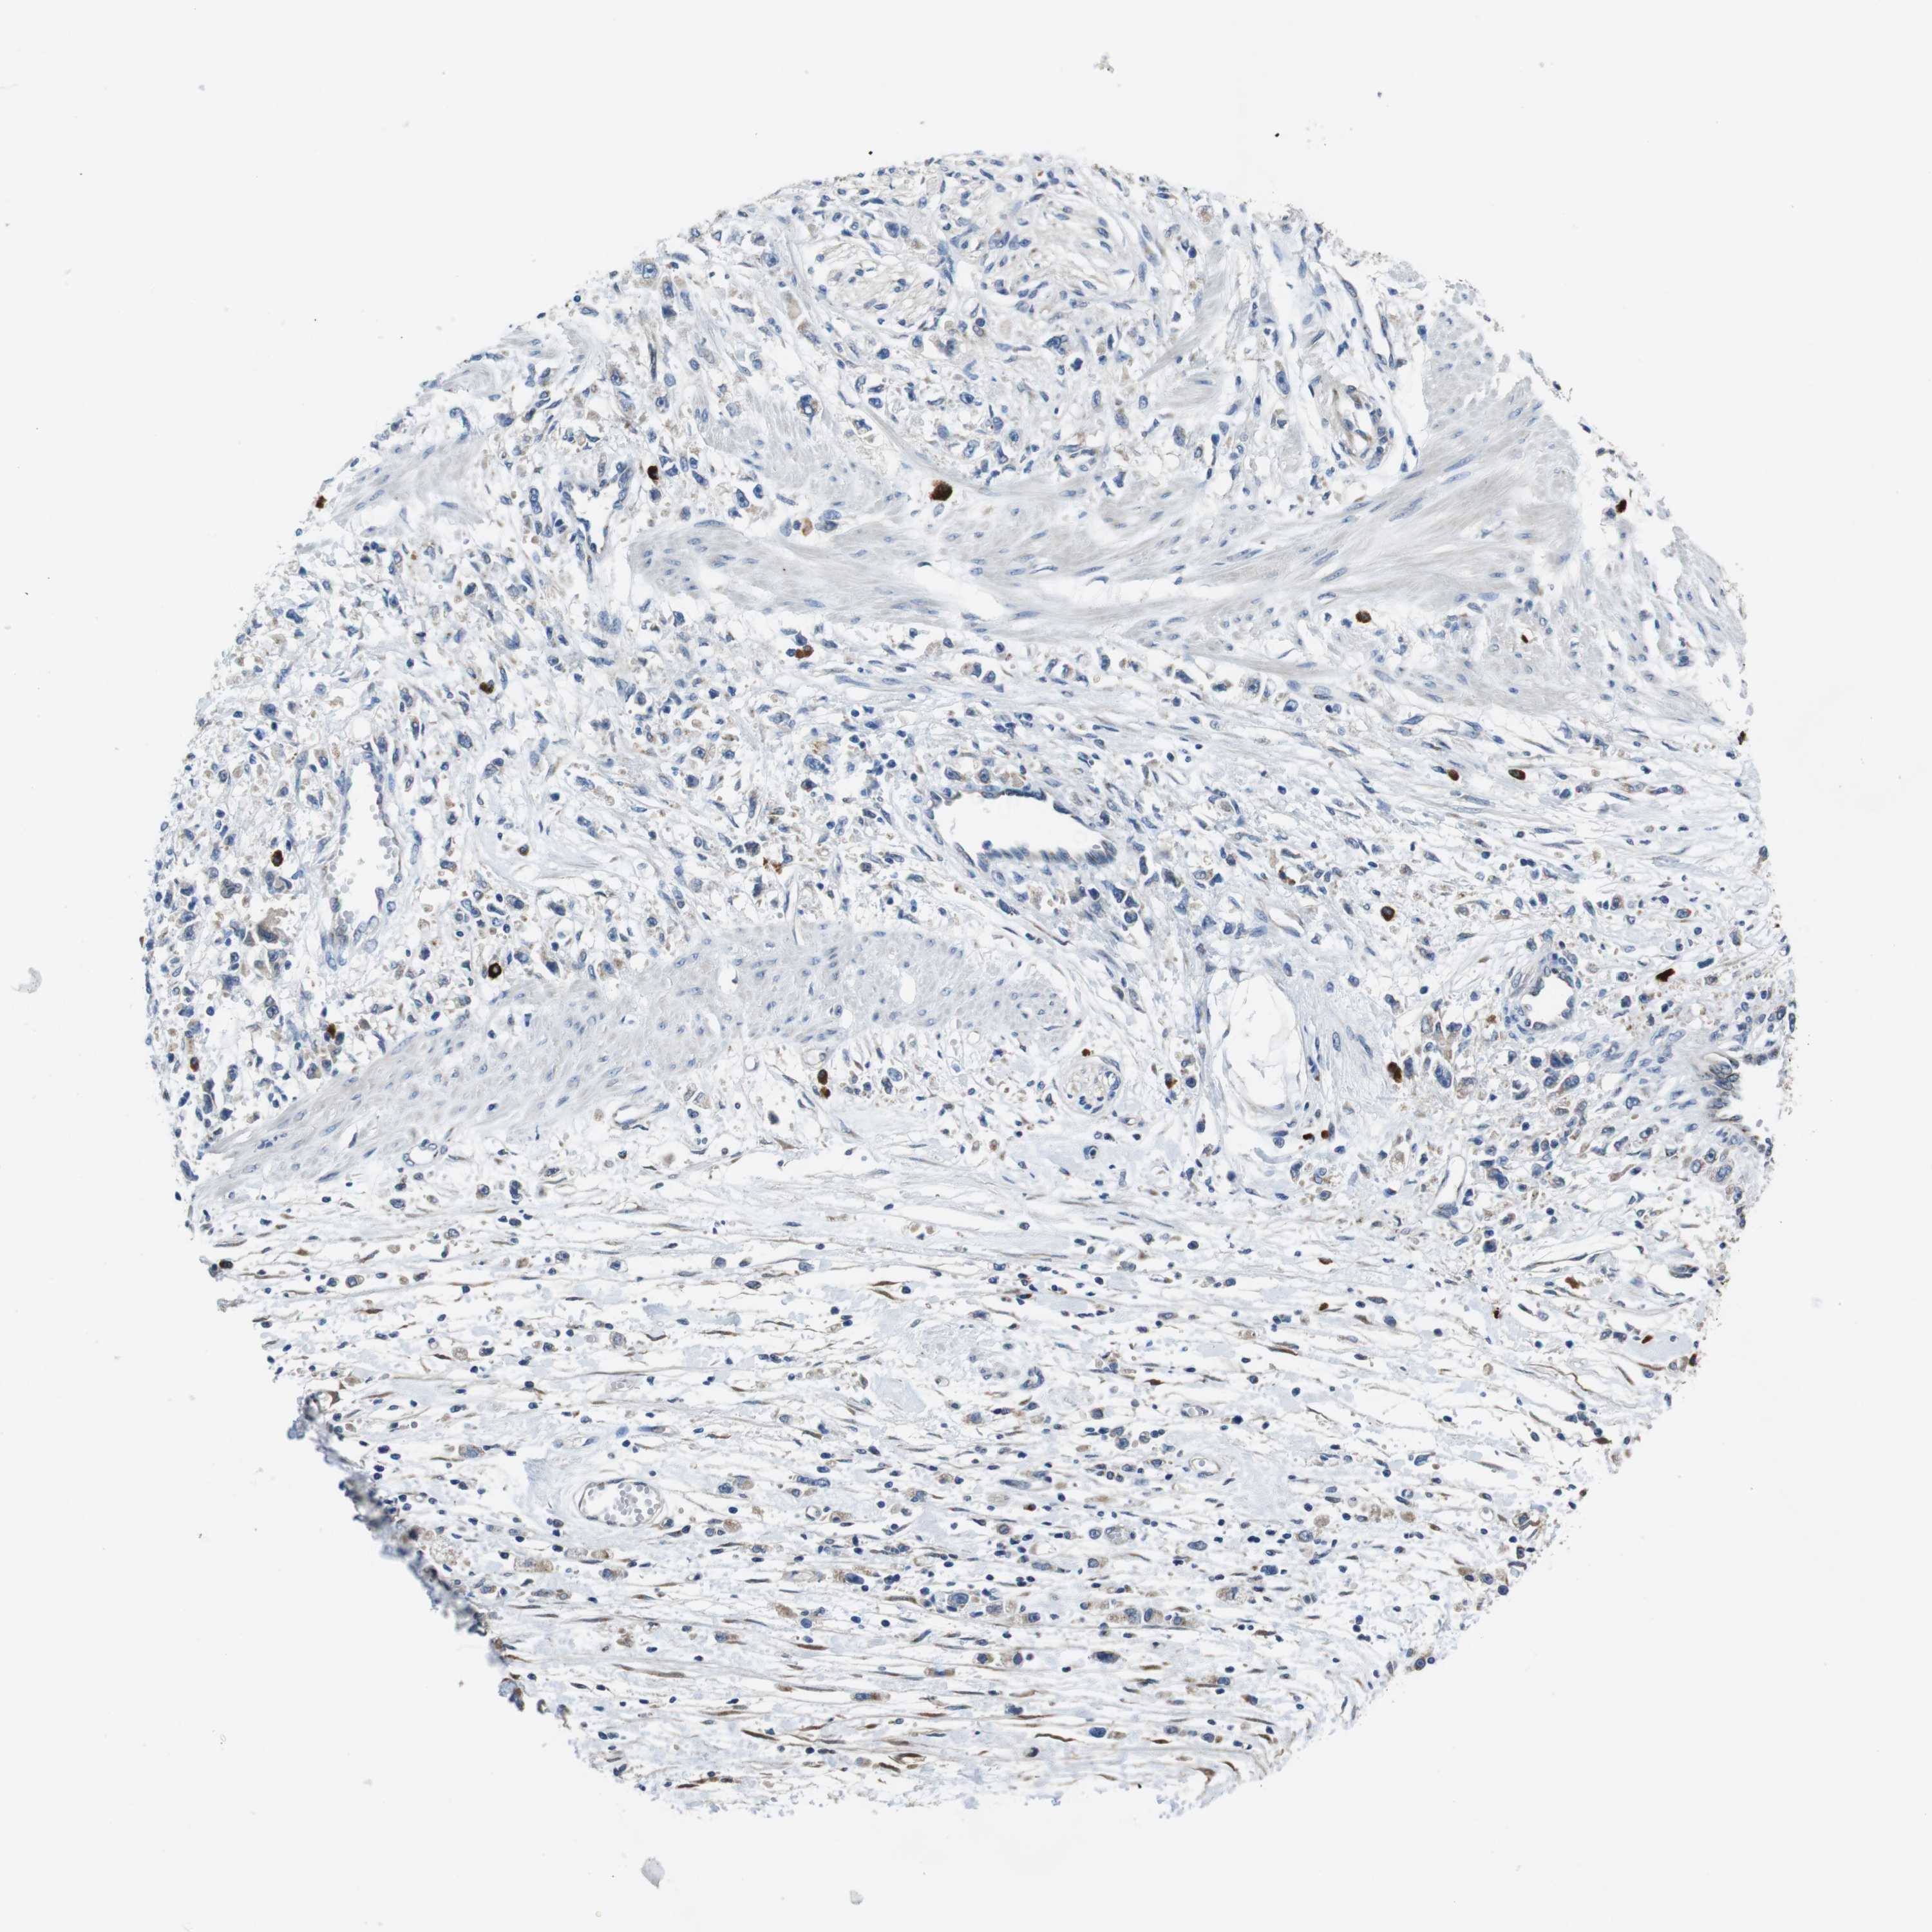

STOMACH CANCER - Protein expressioni

A mouse-over function shows sample information and annotation data. Click on an image to view it in a full screen mode. Samples can be filtered based on level of antibody staining by selecting one or several of the following categories: high, medium, low and not detected. The assay and annotation is described here.

Note that samples used for immunohistochemistry by the Human Protein Atlas do not correspond to samples in the TCGA dataset.

Antibody stainingi

Antibody staining in the annotated cell types in the current human tissue is reported as not detected, low, medium, or high, based on conventional immunohistochemistry profiling in selected tissues. This score is based on the combination of the staining intensity and fraction of stained cells.

Each image is clickable and will lead to virtual microscopy that enables deeper exploration of all samples and also displays staining intensity scores, fraction scores and subcellular localization as well as patient and tissue information for each sample.

Antibody HPA059131

Antibody CAB009936

Staining

High

Medium

Low

Not detected

Intensity

Strong

Moderate

Weak

Negative

Quantity

>75%

75%-25%

<25%

None

Location

Nuclear

Cytoplasmic/membranous

Cytoplasmic/membranous,nuclear

Adenocarcinoma, NOS

Adenocarcinoma, High grade